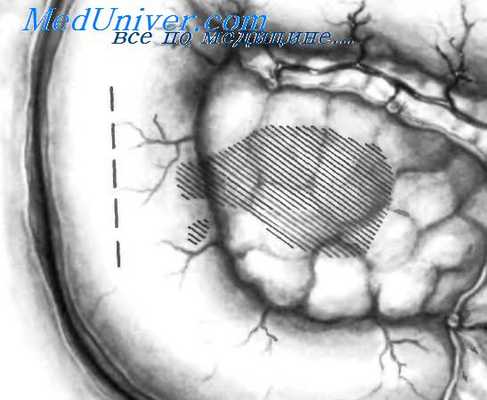

Внепросветные дивертикулы нисходящей части двенадцатиперстной кишки могут развиваться позади поджелудочной железы, как изображено на рисунке.

Реже внепросветные дивертикулы нисходящей части двенадцатиперстной кишки развиваются впереди поджелудочной железы, как показано на рисунке.

В некоторых случаях внепросветные дивертикулы могут развиваться внутри паренхимы поджелудочной железы, как изображено на рисунке. Независимо от того, в каком направлении развиваются дивертикулы, они могут вызвать сдавление общего желчного протока или протока поджелудочной железы, что приводит к таким осложнениям, как желтуха, панкреатит, инфекция и др.

Перед выделением дивертикула необходимо установить его точную локализацию и взаимоотношения сфатеровым сосочком. Это можно сделать до операции и уточнить во время нее. Весьма целесообразно использовать интраоперационную холецистохолангиографию путем пункции желчного пузыря. Затем выполняют мобилизацию двенадцатиперстной кишки и головки поджелудочной железы по Vautrin-Kocher. Мобилизация по Vautnn-Kocher должна быть широкой, с рассечением брюшины у наружного края двенадцатиперстной кишки, причем не только в нисходящей, но также и в верхней горизонтальной части, а также по наружному сегменту нижней горизонтальной части до линии верхней брыжеечной артерии, как показано на рисунке. Затем производят небольшой поперечный разрез на общем желчном протоке, через который вводят резиновый зонд с оливообразным концом